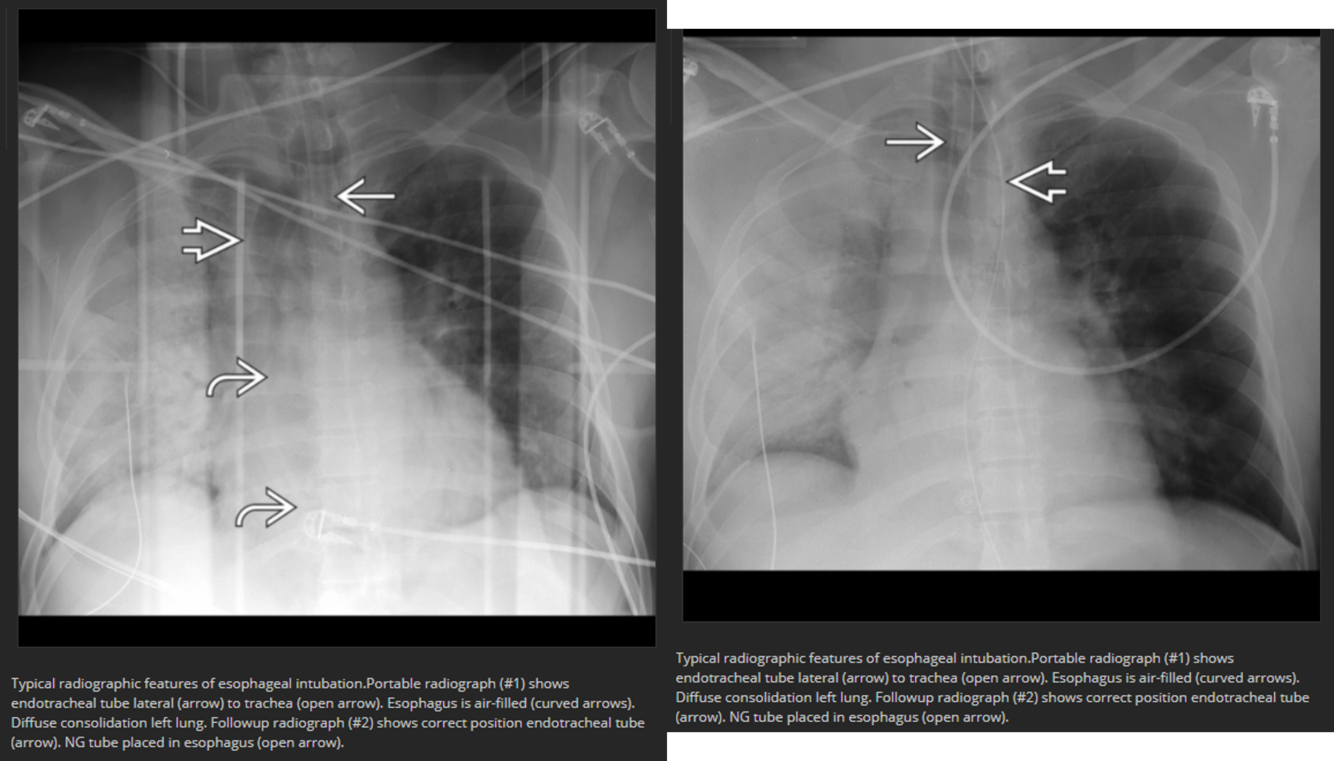

Esophageal intubation